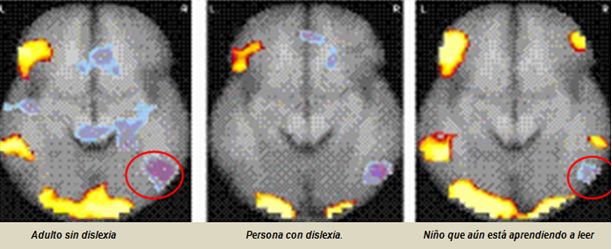

ALTERACIONES NEUROLOGICAS EN LA DISLEXIA

Existen numerosas investigaciones que establecen que la estructura celular del cerebro de una persona con dislexia es diferente.

Gracias a tecnologías como la resonancia nuclear magnética se ha podido comprobar que en la parte del cerebro (el área de Broca) donde se procesa el lenguaje, simplemente no se activa en la persona con dislexia cuando está en proceso de lectura.

En la siguiente imagen podemos ver lo que acabamos de exponer: Es una resonancia magnética nuclear y se hizo en el momento en que tres personas distintas estaban leyendo un texto.

Se puede constatar que la parte del lenguaje que se encuentra en el hemisferio izquierdo medio lateral no se activa.

Estas observaciones apoyan firmemente la hipótesis de que mientras el hemisferio izquierdo de la corteza auditiva humana tiene capacidades superiores de resolución temporal, el hemisferio derecho tiene mejores capacidades de resolución silábica.